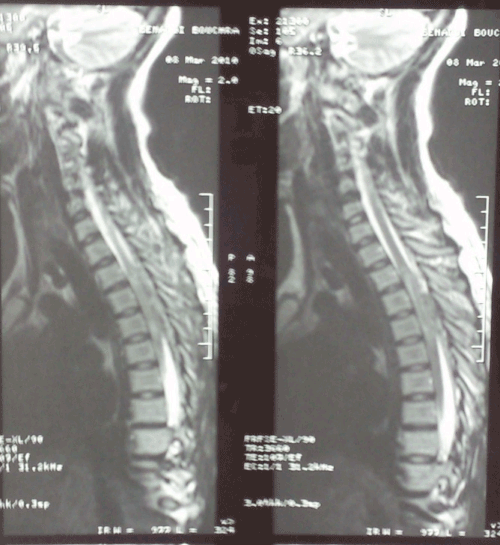

Figure 1: Cervical and thoracic MRI in T1 (sagittal) showing an epidural haematomacompressing the spinal cord from the 2nd to the 4th thoracic vertebrae.